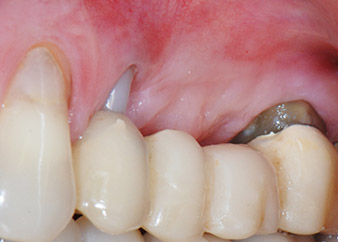

A 58-year-old female patient complained of pain and increased mobility of her bridge abutment tooth 24. Periodontal inflammation was present with pocket depths of 7 mm mesiobuccally and more than 12 mm distally, as well as third-degree furcation involvement. Moreover, the radiograph revealed an extensive periodontal lesion around the apical region of the (alio loco) endodontically pretreated tooth 24 (Fig. 1).

One month later, on the day of surgery, pain and inflammation at tooth 24 were minimal, but mobility of Miller class 2 was still present. After opening the flaps and cleaning the periapical and peri radicular infected tissue, the extent of the bone defect became obvious (Figs. 2 and 3).

At the buccal root, all vestibular and distal bone was missing. Attachment was essentially restricted to the palatal root, underlining the preliminary poor prognosis. Tooth 27 also showed a reduced horizontal attachment and a minimal apical rarefaction (cf. Fig. 1) without clinical symptoms.

total loss of bone and attachment

Fig. 2 and 3: After raising flaps, one month after endodontic revision and initiation of full-mouth periodontal therapy, the buccal root of tooth 24 showed a total loss of bone and attachment.